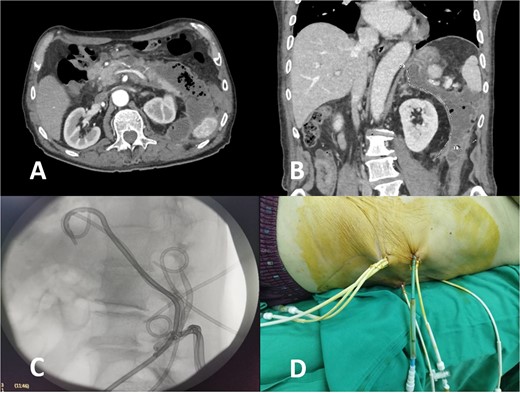

Nine days later, a persistent fever reaching 38.6°C with tenderness in upper abdominal quadrants was presented. In addition, the patient reported significant fatigue and exhibited tachycardia with a heart rate of up to 106 beats per minute. Laboratory findings revealed leukocytosis (15.03 G/L) with neutrophilia (11.84 G/L), moderately elevated serum amylase (394 U/L), and hyperbilirubinemia (total – 31.7 μmol/L, direct – 23.1 μmol/L). Abdominal ultrasound showed an enlarged pancreas with blurred, heterogeneous hypoechoic echostructure, indistinct gland margin, peripancreatic fluid, and walled-off necrosis next to the pancreatic tail, extending laterally to the splenorenal recess, with a longitudinal size of ~10 cm and thick heterogeneous content, suggesting secondary inflammation. Computed tomography (CT) verified gas-containing fluid collections spreading from the pancreas to the left iliac crest (Fig. 1A and B) along with bilateral pleural effusions.

CT image of large infected peripancreatic collections with multiple air locules (A and B) and placed pigtail catheters post-imaging (C and D).

Following well-established guidelines, empiric antibiotic therapy with a carbapenem was started (Meropenem 1 g every 8 hours). The patient underwent PCD with the initial insertion of five drains: two in the peripancreatic collection and three in the pararenal space, with one situated caudal to the lower border of the collection at the level of the iliac crest. Microbiological examination revealed the presence of Meropenem-resistant Escherichia coli, sensitive to Cefoperazone-sulbactam, necessitating a change in antibiotic treatment according to antibiogram results. Continuous postprocedural transcatheter lavage with physiological saline was performed. Follow-up abdominal sonography showed the persistence of a small undrained collection in the posterior pararenal space, leading to the placement of two additional drains in that area (Fig. 1C and D).